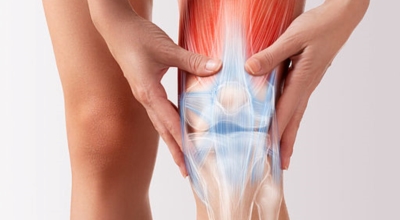

나이가 점점 들수록 보행 속도가 자연적으로 느려지게 되는데, 그 이유는 바로 관절의 노화 때문입니다. 노화가 진행되면 연골 손실이나 관절 간격이 짧아짐에 따라 관절염이 발생하고, 그로 인해 통증이 생겨 보행력이 점점 저하가 될 수 밖에 없다고 합니다. 이 때문에 나이가 들수록 콘드로이친을 보충시켜 주는 것이 보행역량 개선에 도움을 줄 수 있는 방법중 하나 입니다.

콘드로이친에는 관절 통증 감소 효험도 있습니다. 콘드로이친은 보통 관절염으로 인한 무릎 통증을 관리하기 위해 사람들이 많이 필요로 하는 성분입니다. 관절염의 증상을 덜어줄 수는 있지만 섭취로 인한 효과가 영구적으로 지속되지는 않습니다. 그렇기 때문에 별개의 관절염 치료와 복용을 병행하시는 것이 더 좋아요.

콘드로이친 중 가장 대표적인 것이 연골세포를 보존하는 역할이라고 합니다. 콘드로이친에는 연골세포의 분해를 억제시켜 연골세포를 보호해주며 유지시켜주는 기능이 있습니다. 연골은 노화가 진행될수록, 나이가 들 수록 점점 그 크기가 감소하거나 끊어질 수 있지만 이때 콘드로이친이 그 스펀지와 같은 역할을 하여 연골 속 수분을 잡아주어 부드럽고 유연하게 유지할 수 있도록 도와준다고 알려져 있답니다.

하지만 콘드로이친은 신체 내에서 자연적으로 생성을 할 수 없어 외부에서 추가적으로 보충되어줘야 하는데 나이가 들면서 점점 콘드로이친이 부족하게 되면 무릎이나 손목의 통증, 관절염 등 자연 노화로 인해 피할 수 없이 오는 질환들이 발생할 수 있다고 해요. 그뿐 아니라 아침에 일어났을 때 주로 일어나는 관절 경직 증상 완화에도 큰 도움 됩니다.

관절염으로 인한 통증은 환자의 몸의 기능을 쇠약하게 만들기도 합니다. 좀 더 유심히 말하자면, 관절염으로 기인해서 몸을 움직이지 않아 일상 활동과 삶의 질에 영향을 미치게 됩니다. 한 프랑스에서 모두 만들어진 연구에 의하면 12개월간 관절염 환자에게 하루에 800mg의 콘드로이친을 전달한 결과 위약을 복용시킨 대조군에 대조해 기능 역량이 50% 내외로 향상된 결과가 나왔습니다.

또 다른 연구를 보면 콘드로이친 복용이 무릎 관절의 마찰 계수를 낮추는 것으로 보여 집니다. 즉, 연골이 보다 부드럽게 움직일 수 있도록 도와 관절 기능에 도움이 되는 것 이예요.